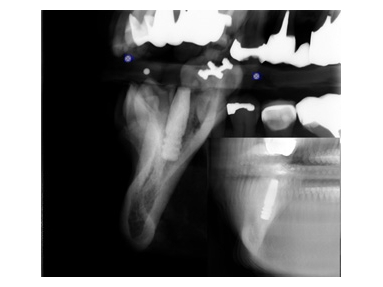

個々の歯を診るのはセンサータイプのレントゲン↑ですが、IPタイプのレントゲンと比較して高解像度のためかなりはっきりと画像が瞬時に見ることができ、正確な判断と待ち時間の短縮、被曝線量の低減を可能にしています。